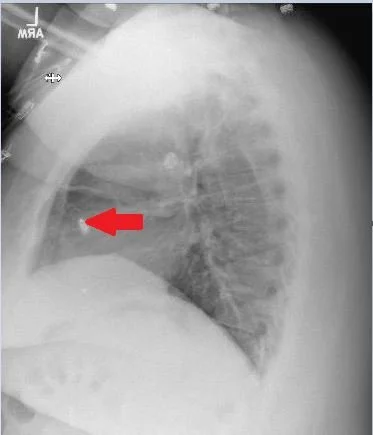

Our patient had a leadless pacemaker which was malfunctioning with spikes on the t waves.

The leadless pacemaker is 90% smaller than a transvenous pacemaker and is a self contained generator and electrode system implanted by catheter into the RV.  It lasts 6-12 years.  It is used mainly for  a fib with bradycardia, tachy brady syndrome or those who infrequently require pacing. The Micra attaches to the RV with four linear sef-expanding nitinol tines. (titanium-nickel)  Nitinol can deform 10-30 times as much as ordinary metals and return to its original shape.

placement by catheter in the RV

The Medtronic micra is 2.59 x 6.7 mm